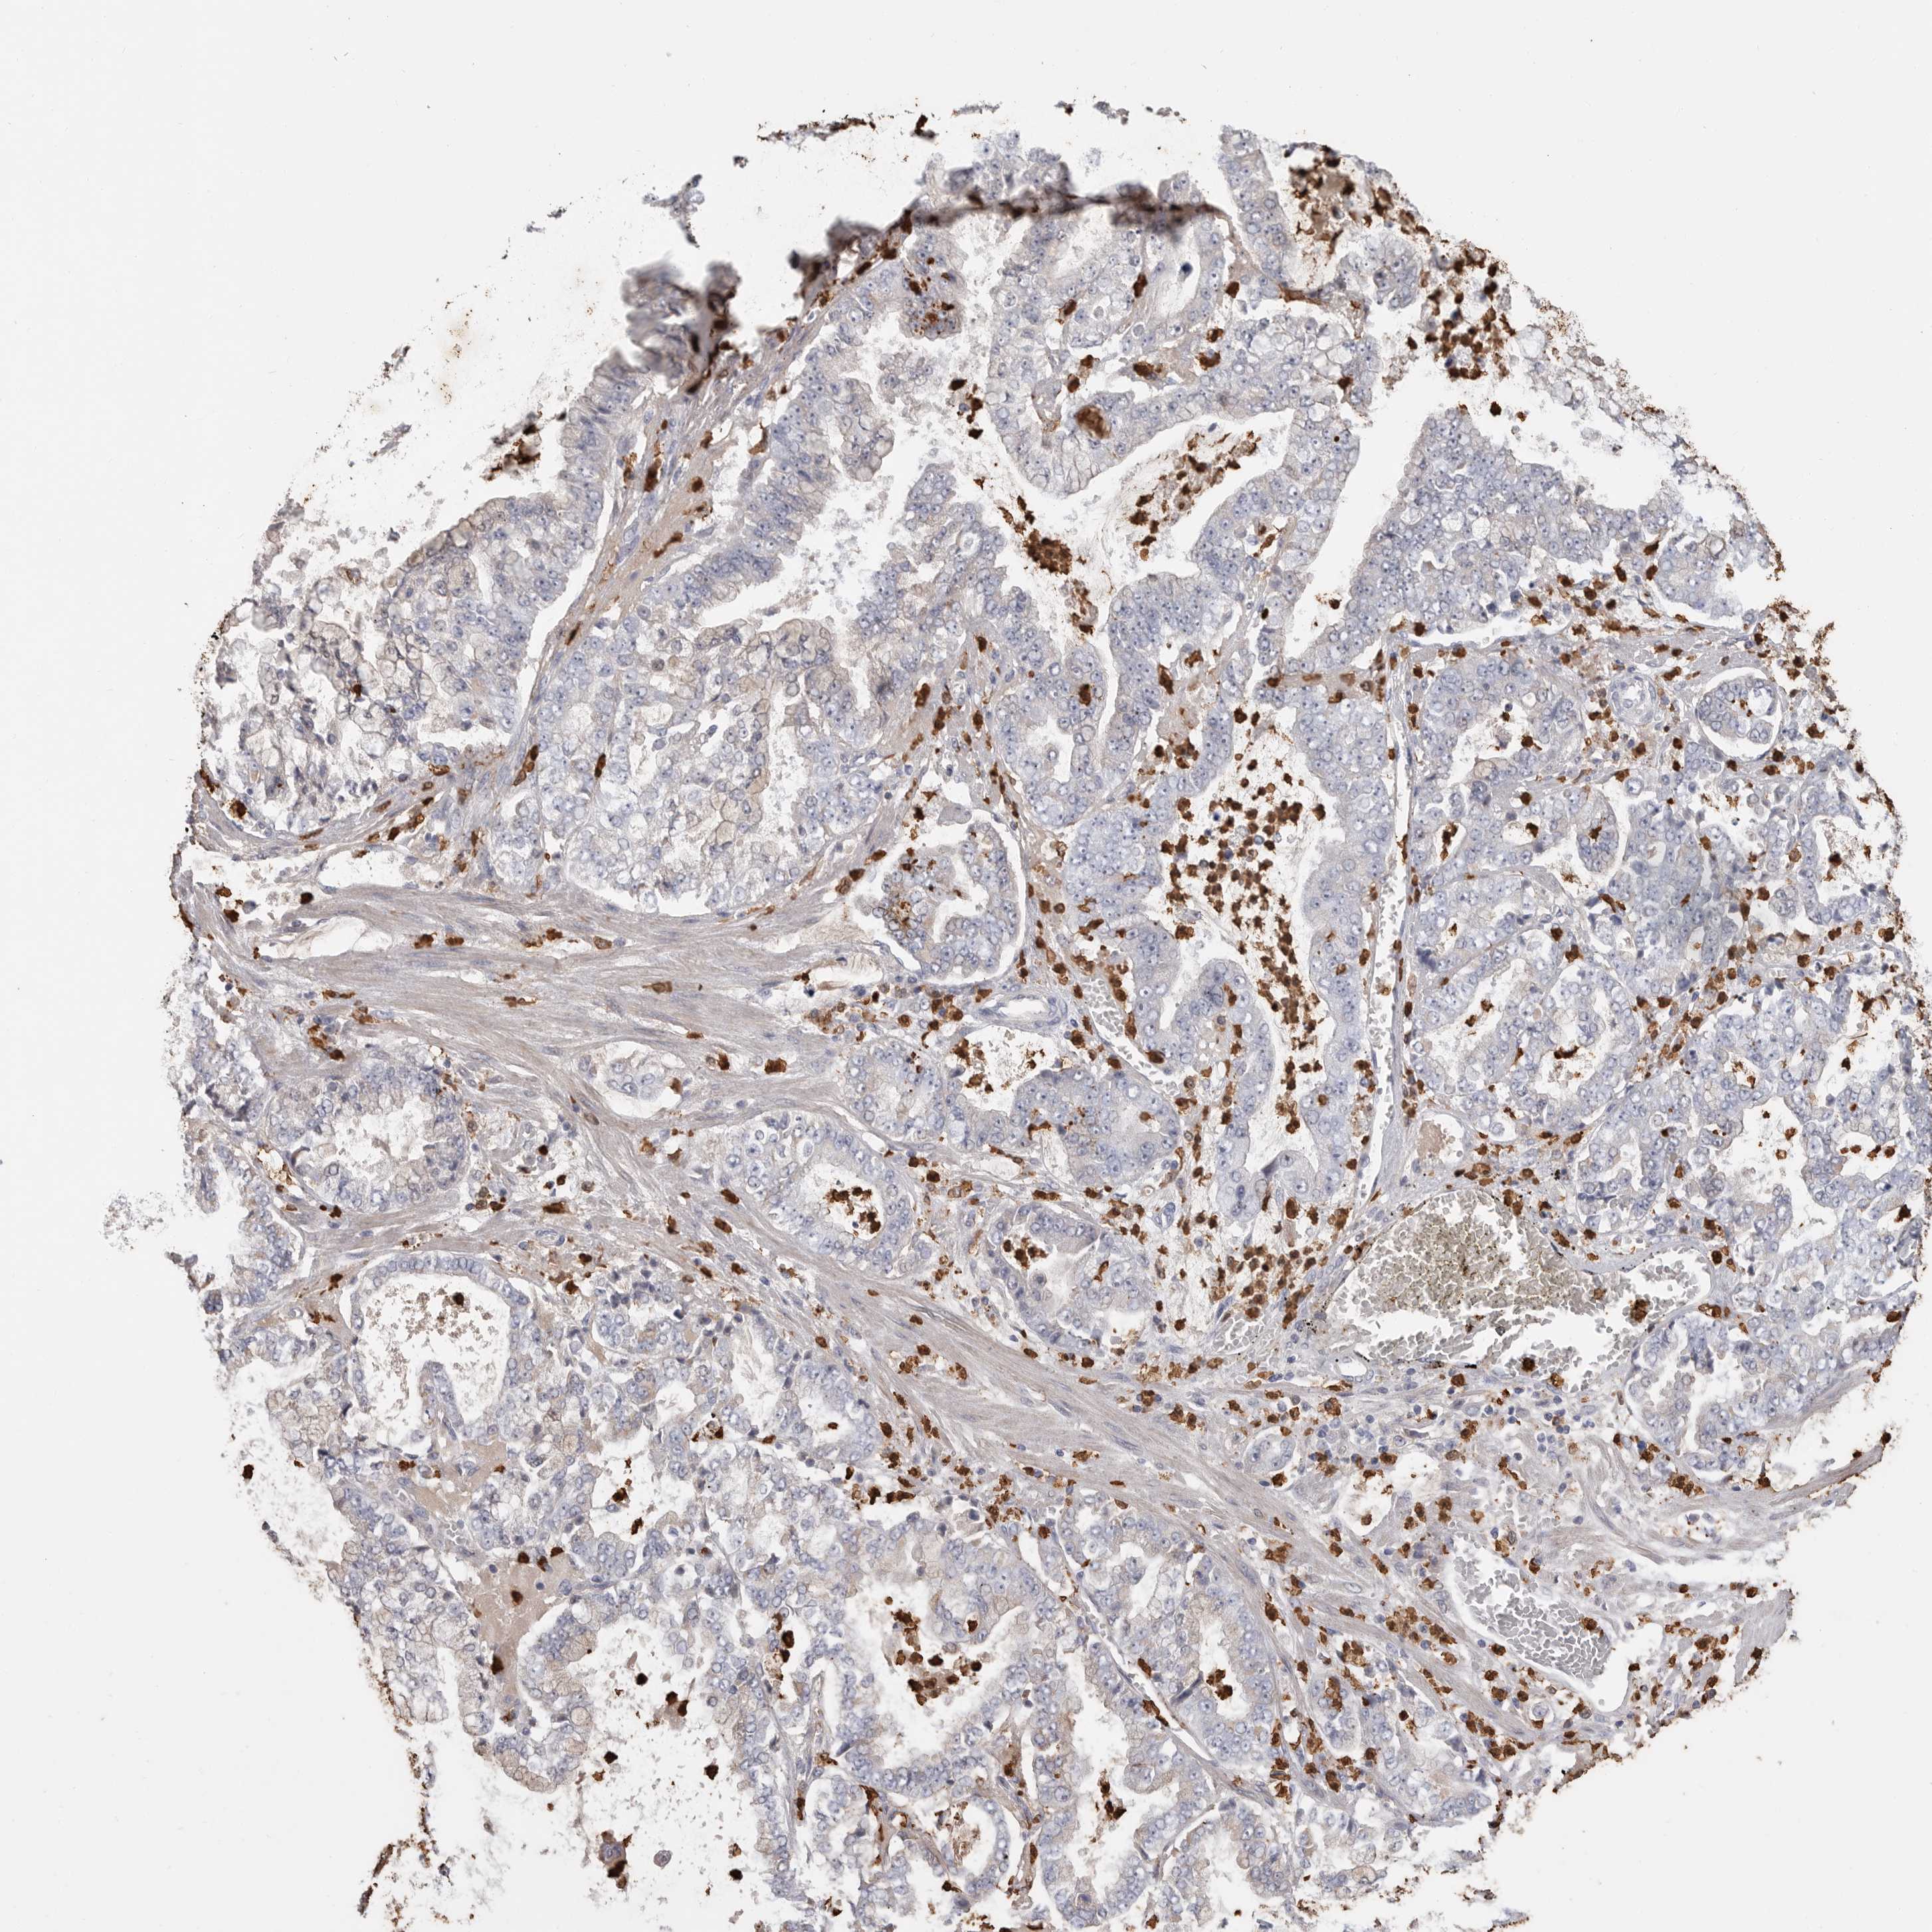

STOMACH CANCER - Protein expressioni

A mouse-over function shows sample information and annotation data. Click on an image to view it in a full screen mode. Samples can be filtered based on level of antibody staining by selecting one or several of the following categories: high, medium, low and not detected. The assay and annotation is described here.

Note that samples used for immunohistochemistry by the Human Protein Atlas do not correspond to samples in the TCGA dataset.

Antibody stainingi

Antibody staining in the annotated cell types in the current human tissue is reported as not detected, low, medium, or high, based on conventional immunohistochemistry profiling in selected tissues. This score is based on the combination of the staining intensity and fraction of stained cells.

Each image is clickable and will lead to virtual microscopy that enables deeper exploration of all samples and also displays staining intensity scores, fraction scores and subcellular localization as well as patient and tissue information for each sample.

Antibody HPA027028

Staining

High

Medium

Low

Not detected

Intensity

Strong

Moderate

Weak

Negative

Quantity

>75%

75%-25%

<25%

None

Location

Nuclear

Cytoplasmic/membranous

Cytoplasmic/membranous,nuclear

Adenocarcinoma, NOS